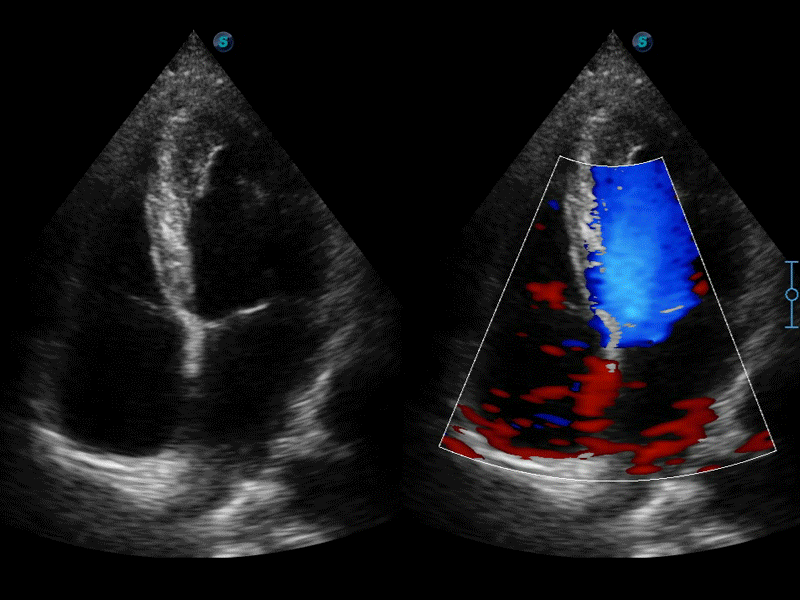

彩色多普勒超声诊断系统

高分辨率血流成像技术提高了对低速血流信号的检测能力。在提高空间分辨率的同时,也克服了血流外溢现象,为用户提供更加真实的血流动力学信息。